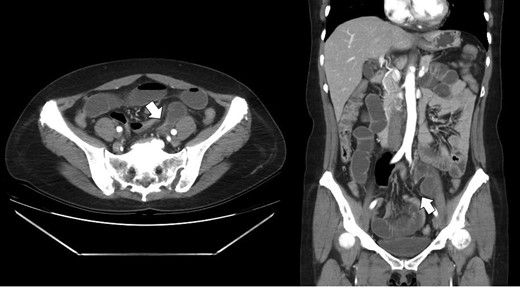

Laboratory data were unremarkable. Abdominal X-rays showed slight distension of small bowels with air-fluid levels (Fig. 1). CT scan revealed that dilated small bowel loops probably ileal level in left lower quadrant (Fig. 2). A nasogastric tube was inserted and she was given a conservative treatment over the next 2 days, but we proposed a laparoscopic exploration because of no clinical improvement.

Contrast enhanced CT showing the transitional zone (white arrow) between dilated to collapsed loops in the left lower abdomen.